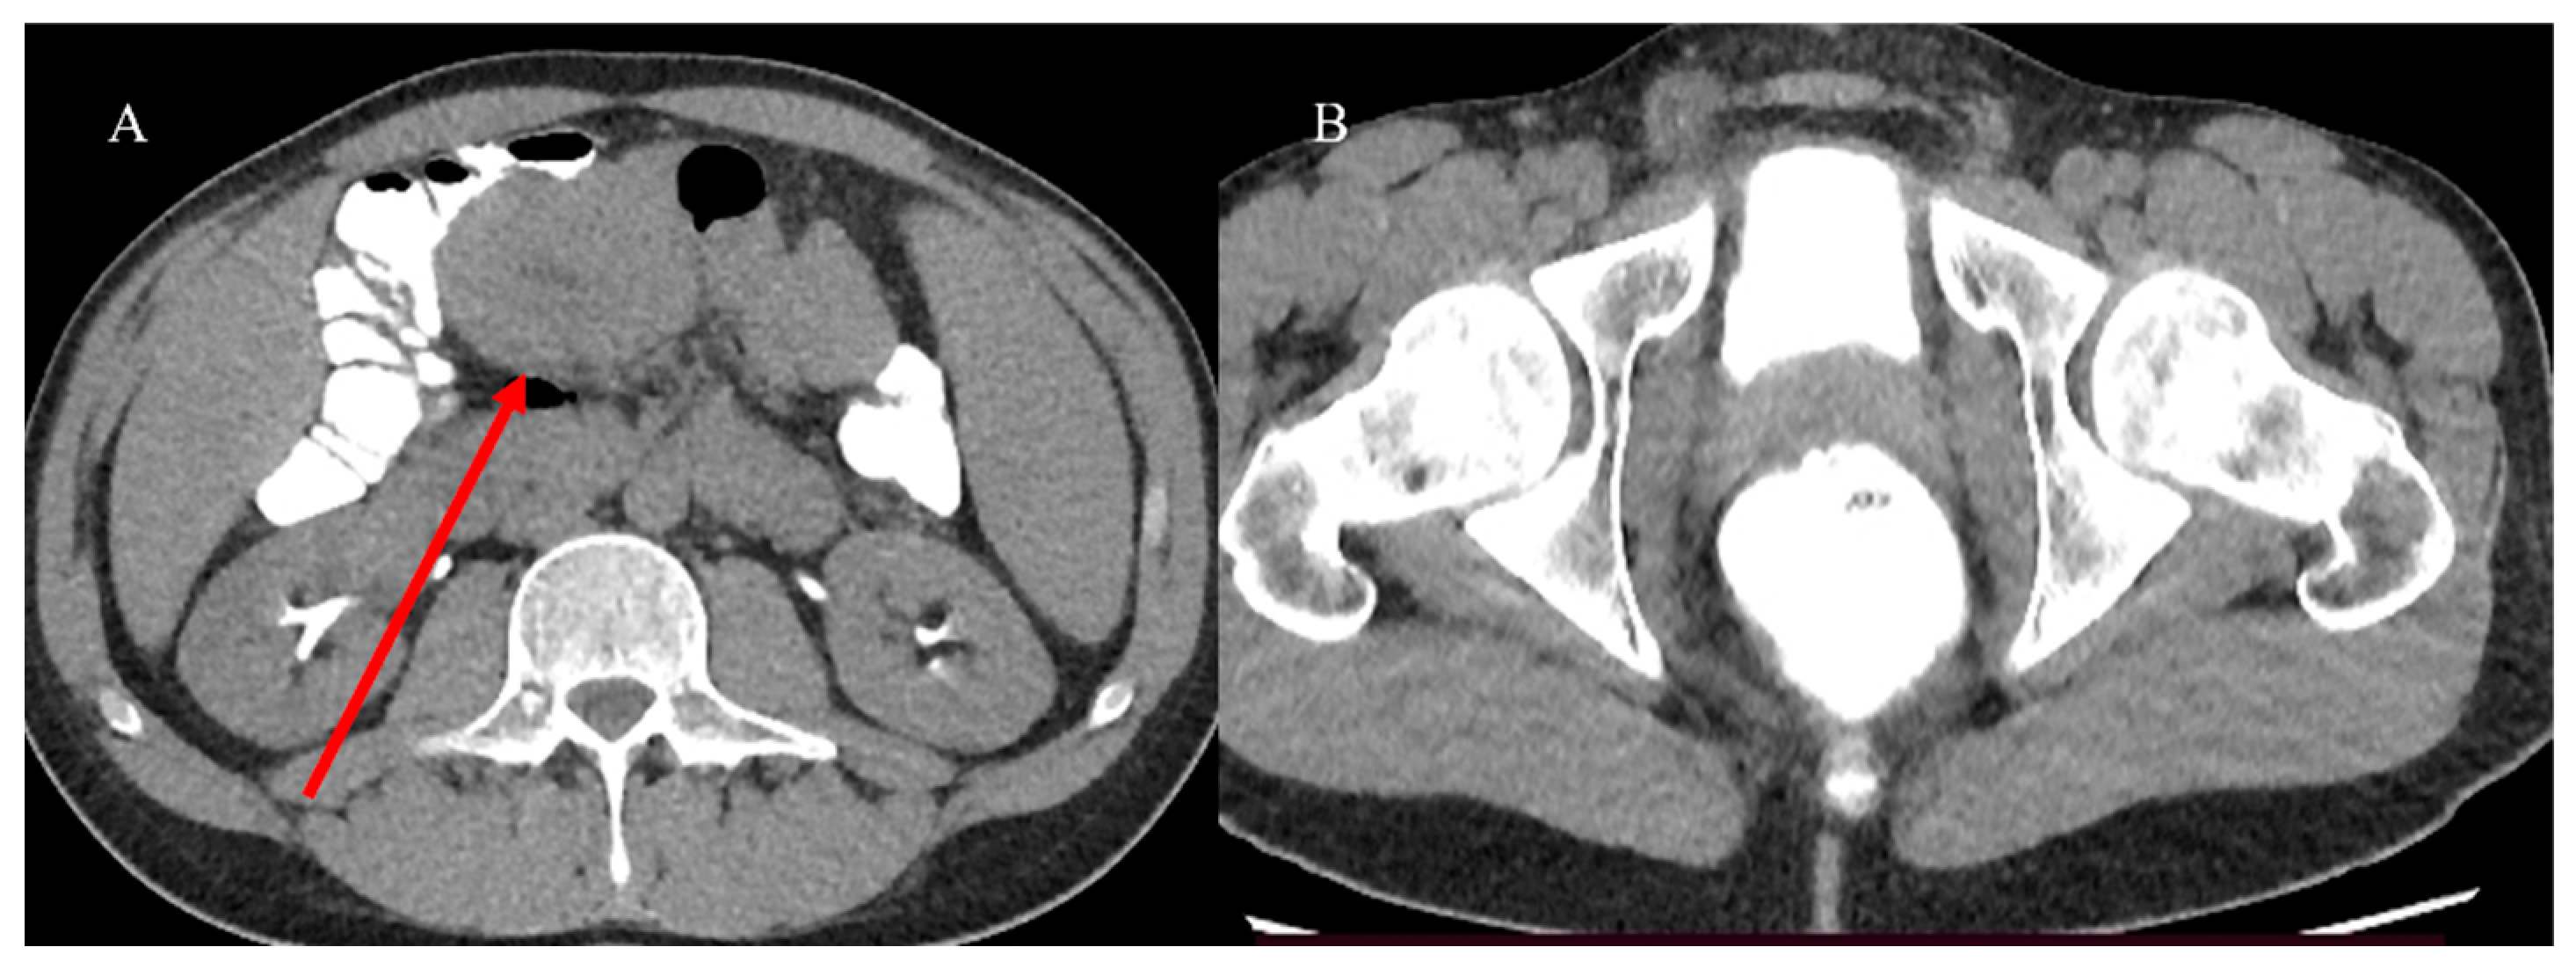

- Tuca, A.; Guell, E.; Martinez-Losada, E.; Codorniu, N. Malignant bowel obstruction in advanced cancer patients: Epidemiology, management, and factors influencing spontaneous resolution. Cancer Manag. Res. 2012, 4, 159–169. [Google Scholar] [CrossRef]

- Alshamsan, B.; Aseafan, M.; Badran, A.; Shaheen, A.; Elshenawy, M.A.; Bazarbashi, S.; Aljubran, A.H. Characteristics and outcomes of small bowel adenocarcinoma: 14 years of experience at a single tertiary hospital in Saudi Arabia. Mol. Clin. Oncol. 2023, 18, 17. [Google Scholar] [CrossRef]

- Kroepfl, V.; Bellotti, R.; Gasser, E.; Esswein, K.; Esser, H.; Kafka-Ritsch, R.; Öfner, D.; Perathoner, A. Small bowel neuroendocrine tumors: An analysis of clinical presentation, diagnostic workup and surgical approach—A single center retrospective study. Front. Surg. 2023, 10, 1072435. [Google Scholar] [CrossRef]

- Basendowah, M.H.; Ashour, M.A.; Hassan, A.Y.; Alshaynawi, S.; Alyazidi, L.K. Multiple small intestinal neuroendocrine tumors with findings of intestinal obstruction. Cureus 2021, 13, e17629. [Google Scholar] [CrossRef] [PubMed]

- Nelms, D.W.; Kann, B.R. Imaging modalities for evaluation of intestinal obstruction. Clin. Colon. Rectal Surg. 2021, 34, 205–218. [Google Scholar] [CrossRef]

- Paulson, E.K.; Thompson, W.M. Review of small-bowel obstruction: The diagnosis and when to worry. Radiology 2015, 275, 332–342. [Google Scholar] [CrossRef] [PubMed]